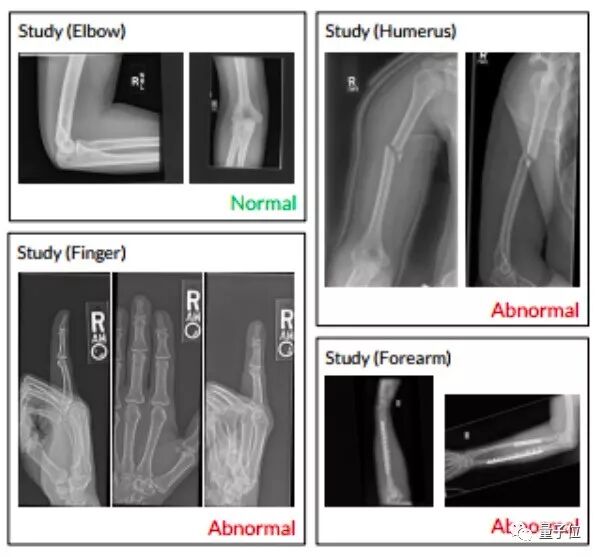

△ 人工标注的4万张X光片。左上,正常的手肘;右上,骨折的上臂;左下,骨骼退化的指端;右下,打了钢板和钢钉的尺骨和桡骨。

这四万张图来自近15000篇论文,其中9067篇为正常上肢骨骼肌X光片的研究,5915篇是异常研究。上肢包括肩膀、肱部、手肘、前臂、手腕、手、指端。